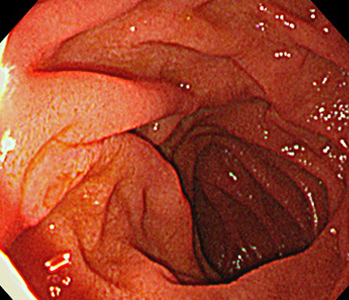

胃内視鏡(胃カメラ)画像

| ◆ 経口内視鏡(高解像度)◆ | ◆ 経鼻内視鏡 ◆ |

| 胃 | 胃(経鼻) |